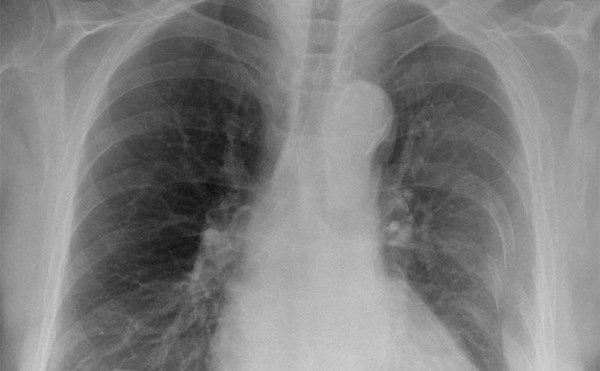

Pulmonary Embolism s/p surgery

A 46 year old male with a cast on his left leg from an ankle fracture presents to the ED complaining of pleuritic chest pain and shortness of breath.